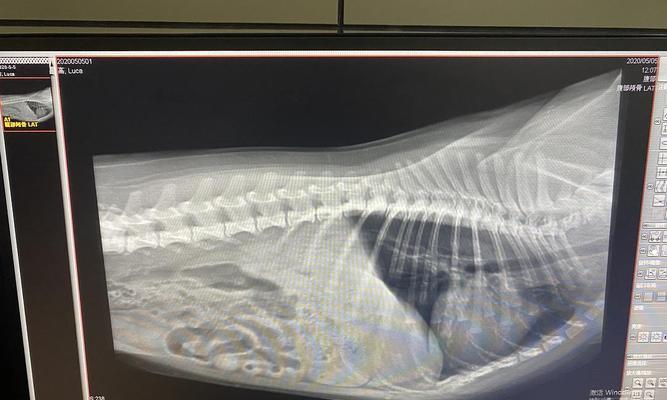

常见症状5:腹部膨胀(胃抽搐症状之五:腹部膨胀)